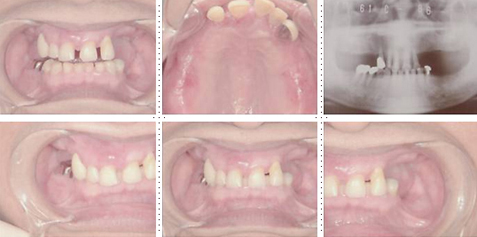

症例2

62才 女性

上顎は総義歯、下顎はブリッジと局部床義歯が装着。義歯は違和感があり、食事も不便を感じ、審美的にも人前にでるのが苦痛に感じていました。この状態を打破するためにも、「インプラント治療に自分の人生を賭けてみたい」という覚悟で来院されました。インプラント手術に対する恐怖心も強くお持ちでした。このような骨幅が狭いケースでは、X線撮影と共にCT撮影による画像診断とインプラント埋入シミュレーションが重要です。

下顎は両側犬歯を残し、他は抜歯。インプラント7本埋入。 上顎はインプラント8本埋入。 インプラント手術を受けられる患者さんは、前の晩眠れない程の不安感、恐怖心を持って来院されます。実際には麻酔注射は痛みを感じず、インプラント手術も痛みも無く、短時間(1本平均3分)で終わるという、当院独自のテクニックにより、2回目からのインプラント手術は気楽になるようです。 前歯は仮歯の段階で患者さん、歯科医、技工士の三者で、審美性・機能性の面から10回以上形態修正を繰り返し検討した後、上・下顎共に前歯・小臼歯はセラミック(MB)クラウン、大臼歯はゴールドクラウンを装着。ご本人とご家族の方にも、「アンチエイジングには、審美インプラント治療が一番効果あり」と大変喜んで頂きました。